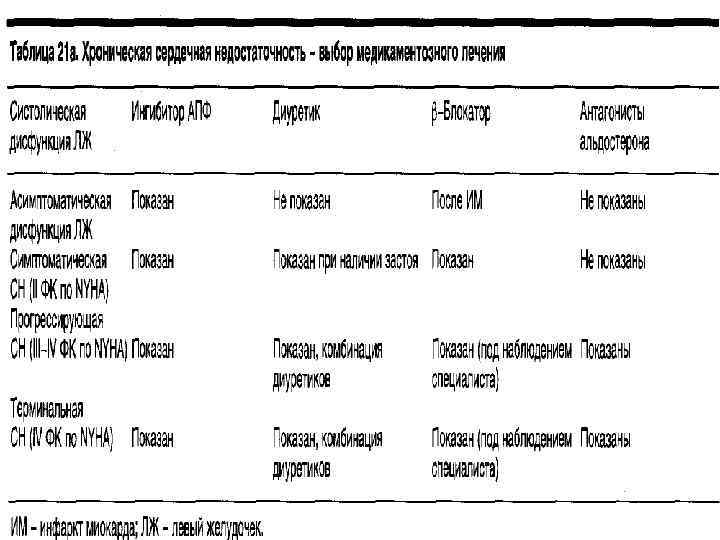

Медикаментозная терапия. Все лекарственные препараты, применяемые при ХСН делят на: ОСНОВНЫЕ – эффект которых доказан, не вызывает сомнений и которые рекомендованы к применения во всем мире (ИАПФ – всем больным, независимо от стадии, этиологии, распространенности процесса и типа декомпенсации;

Медикаментозная терапия. Все лекарственные препараты, применяемые при ХСН делят на: ОСНОВНЫЕ – эффект которых доказан, не вызывает сомнений и которые рекомендованы к применения во всем мире (ИАПФ – всем больным, независимо от стадии, этиологии, распространенности процесса и типа декомпенсации;

МЕДИКАМЕНТОЗНАЯ ТЕРАПИЯ ХСН диуретики – показаны всем больным при клинически значимых симптомах декомпенсации, связанных с избыточной задержкой натрия и воды в организме; сердечные гликозиды – в малых дозах и с осторожностью при синусовом ритме, при МА – средства выбора; β-адреноблокаторы – применяются «сверху» , дополнительно к ингибиторам ИАПФ; антагонисты рецепторов к альдостерону (альдактон);

МЕДИКАМЕНТОЗНАЯ ТЕРАПИЯ ХСН диуретики – показаны всем больным при клинически значимых симптомах декомпенсации, связанных с избыточной задержкой натрия и воды в организме; сердечные гликозиды – в малых дозах и с осторожностью при синусовом ритме, при МА – средства выбора; β-адреноблокаторы – применяются «сверху» , дополнительно к ингибиторам ИАПФ; антагонисты рецепторов к альдостерону (альдактон);

МЕДИКАМЕНТОЗНАЯ ТЕРАПИЯ ХСН ДОПОЛНИТЕЛЬНЫЕ препараты (эффективность и безопасность исследованы и требуют уточнения) антагонисты рецепторов к ангиотензину II (АРА) – используются у больных плохо переносящих ИАПФ; ВСПОМОГАТЕЛЬНЫЕ препараты (влияние на прогноз неизвестно, применение диктуется клиникой (периферические вазодилататоры (нитраты) – при сопутствующей стенокардии; блокаторы кальциевых каналов при упорной стенокардии и АГ; аспирин и другие антиагреганты для вторичной профилактики после перенесенного ОИМ; непрямые антикоагулянты – при риске тромбоэмболических осложнений, особенно у больных с МА, дилатации сердца; статины – при гипер- и дислипопротеидемиях.

МЕДИКАМЕНТОЗНАЯ ТЕРАПИЯ ХСН ДОПОЛНИТЕЛЬНЫЕ препараты (эффективность и безопасность исследованы и требуют уточнения) антагонисты рецепторов к ангиотензину II (АРА) – используются у больных плохо переносящих ИАПФ; ВСПОМОГАТЕЛЬНЫЕ препараты (влияние на прогноз неизвестно, применение диктуется клиникой (периферические вазодилататоры (нитраты) – при сопутствующей стенокардии; блокаторы кальциевых каналов при упорной стенокардии и АГ; аспирин и другие антиагреганты для вторичной профилактики после перенесенного ОИМ; непрямые антикоагулянты – при риске тромбоэмболических осложнений, особенно у больных с МА, дилатации сердца; статины – при гипер- и дислипопротеидемиях.